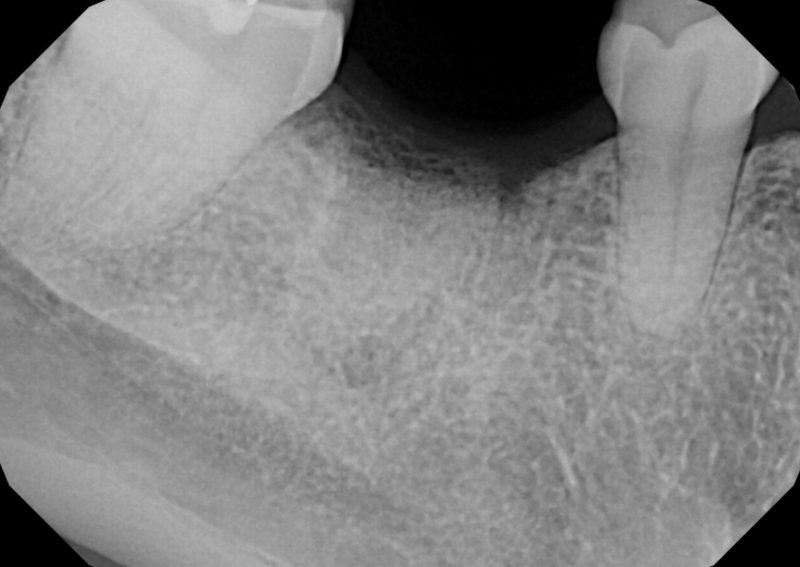

TREATMENT: DENTAL IMPLANT & CROWN

Patient: Sol

A year before visiting us at Riverside Tooth Co., Sol had a damaged tooth extracted. Since that procedure, Sol had gone an entire year without chewing on one side of her mouth. With expert implant placement and restoration, Dr. Sandhu was able to restore the aesthetics of her smile and her ability to chew her favorite foods.